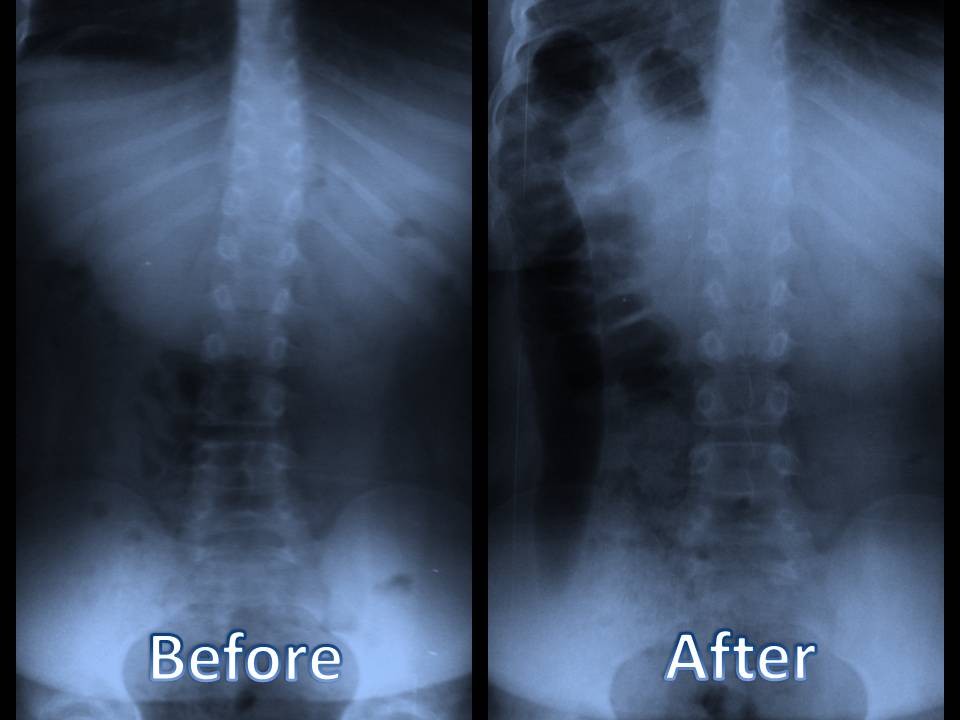

Your doctor may additionally suggest a collection of imaging treatments to establish the source of your pain in the back. These imaging treatments can include x-rays, bone scans, and CT scans. These imaging procedures can be handy, yet they aren't always needed for the majority of instances of back pain. If you have serious neck and back pain, your physician might recommend a shot. These shots can aid to eliminate pain and also decrease swelling.

3. Diagnosis of Back Pain